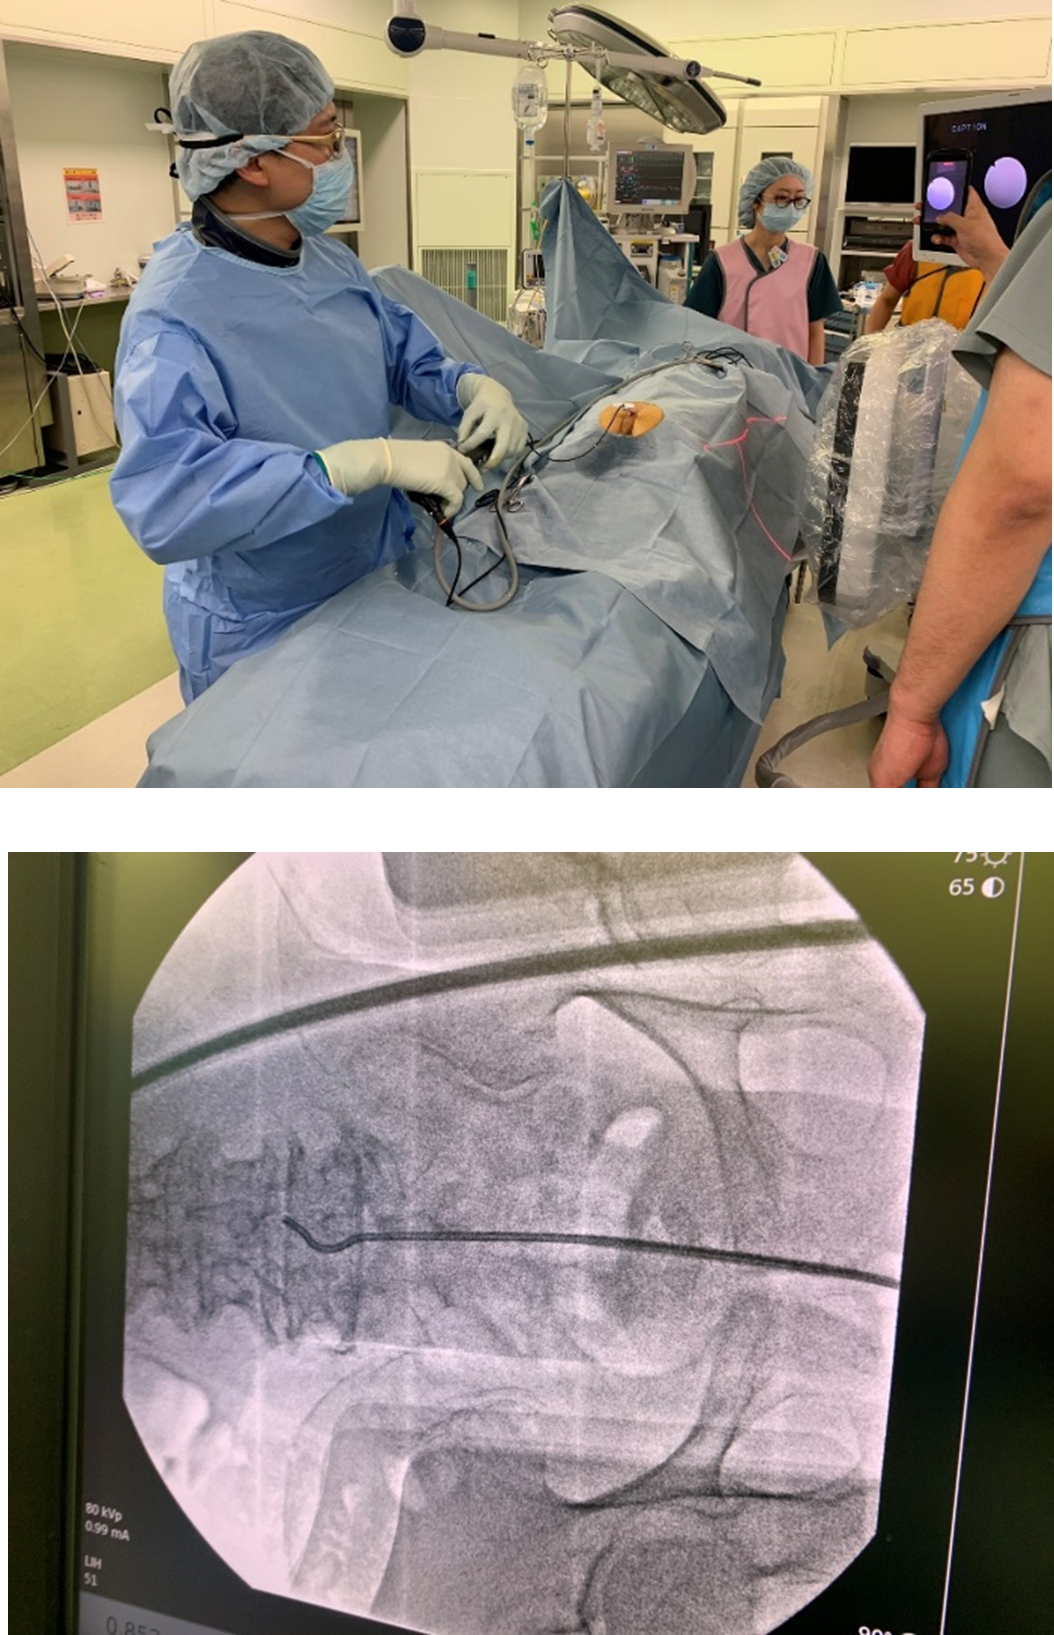

TSCP  経仙骨的脊柱管形成術(Trans-Sacral Canal Plasty)

経仙骨的脊柱管形成術(TSCP)は、今日存在する脊椎内視鏡手術のなかで、最も身体の負担が少ない治療の1つである。局所麻酔、小切開(約3-4㎜)、小出血量、日帰り手術が可能などの観点から全てにおいて最小侵襲である。ただし、国内外でも導入している施設は限定される。手術の適応は、腰椎疾患が主体となるが、腰椎椎間板ヘルニア、腰部脊柱管狭窄症、腰椎変性すべり症、腰椎分離すべり症、腰椎変性側弯症、腰椎滑膜のう腫、腰椎手術後の再発など、多岐にわたる。脊柱管(神経の通り道)に通ずる骨盤の仙骨裂孔という小さな孔から細いカテーテルを挿入し、カテーテルで物理的に、また生理食塩水や薬物などにより神経周囲の剥離を行う。さらには、極細の内視鏡で観察しながら、剥離などを行う事も自由診療で行われている。内服などの薬物療法・神経ブロック・リハビリテーションなどで改善しない例、高齢者で心肺機能の低下により全身麻酔がかけられない例、入院する時間的猶予のない例など適応も広い。

TSCP内視鏡挿入外観 石井賢医師@NSCtky:TSCP内視鏡挿入外観 石井賢医師@NSCtky - YouTube